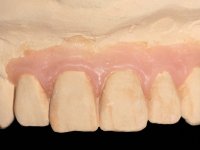

O paciente foi observado conjuntamente e a dúvida que surgiu de imediato foi se seria possível com a regeneração óssea a efectuar poder ser reabilitada naturalmente a zona das papilas interdentárias. Nesse sentido foi feito um enceramento de diagnóstico que contemplaria as duas hipóteses, utilizando ou não a cerâmica gengival. A confecção desse enceramento foi fundamental para expor ao paciente a dificuldade da reabilitação. O wax-up deu origem a um mock-up que foi aprovado pelo paciente e que simultaneamente serviu de guia imagiológica. O caso foi planificado cirurgicamente e realizada uma guia cirúrgica com que foram colocados os implantes. Após 10 semanas foi feita a 1ª impressão para confecção da ponte provisória. Foram criados os primeiros perfis de emergência na gengiva artificial e foi digitalizado o modelo. Por processo de CAD-CAM foi confeccionada uma ponte provisória aparafusada baseada no enceramento de diagnóstico. A ponte trabalhou durante 8 semanas os tecidos moles que foram fielmente copiados numa impressão com técnica de moldeira aberta. Os transferes foram individualizados com resina composta para copiarem fielmente os perfis de emergência criados pela ponte provisória. Confeccionado o modelo de trabalho definitivo, foi realizada uma infra-estrutura em zircónio seguindo a orientação do enceramento de diagnóstico. O assentamento da infra-estrutura foi testado em boca e simultaneamente foi novamente impressionados os tecidos moles com um silicone fluido. Nessa consulta foi feito o levantamento da cor. Os dentes 13 e 23 apresentavam uma saturação anormalmente forte que resolvemos não valorizar, optando por privilegiar a relação com o sector antero-inferior. Foi realizada uma nova gengiva artificial com a impressão que acompanhou a impressão de arrasto com a infra-estrutura. Após a colocação da cerâmica na infra-estrutura foram coladas as meso-estruturas. O trabalho final foi aparafusado lentamente permitindo a adaptação dos tecidos moles.